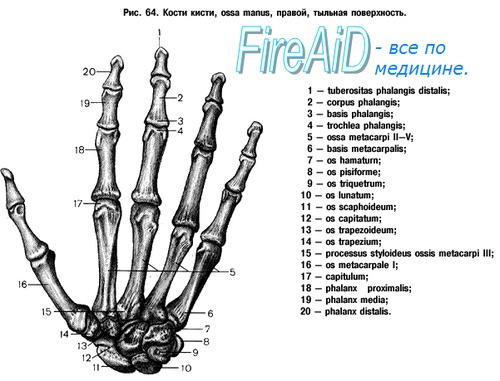

Анатомия кисти руки и строение костей